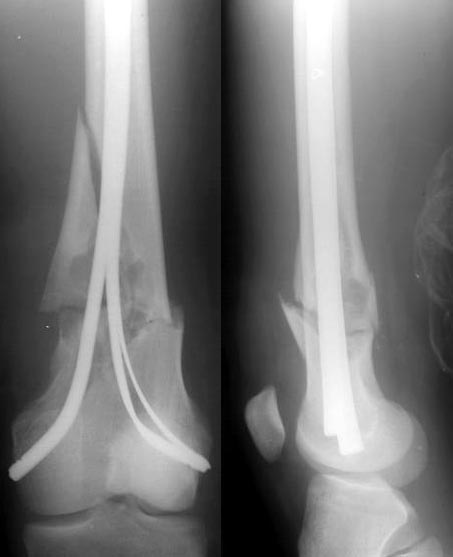

The fracture was fixed yesterday with some retrograde flat titanium nails. I tried to insert a pair of thick ones, but it resulted with fragmentation of the medial cortex above the fracture so i replaced the lateral one with two more thin plates. Fixation is stable under image intensifier. Biopsy was taken. Images attached.

Best regards,